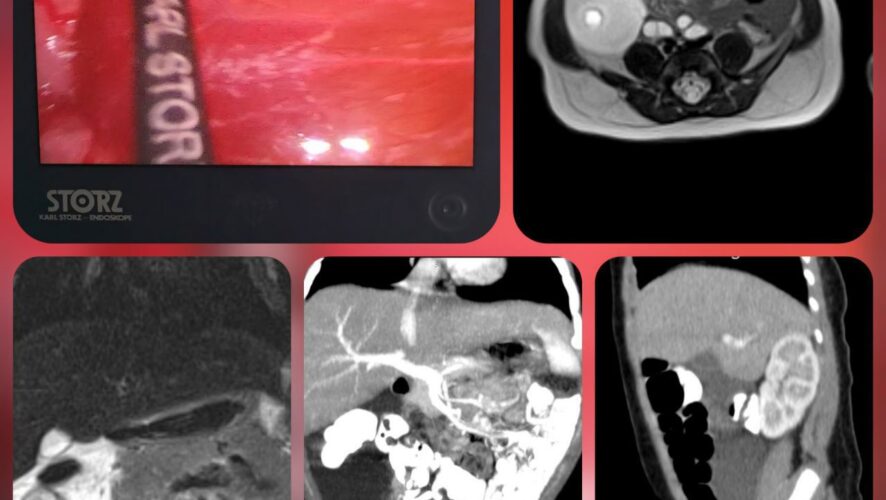

Ребенок был экстренно госпитализирован в отделение хирургии детей раннего возраста с жалобами на крупное кистозное образование в брюшной полости, которое было выявлено ещё во время внутриутробного ультразвукового исследования.

Специалисты отделения после комплексного обследования подтвердили редчайшую аномалию развития лимфатических сосудов, локализованную в брыжейке толстой кишки. Подобные случаи встречаются крайне редко – примерно в 4 на 100 000 госпитализаций, и чаще всего образования обнаруживаются в области шеи или подмышечных впадин. Лечение таких патологий сопряжено с высоким риском серьёзных осложнений, включая воспаления, перфорации и лимфоистечения.

Малоинвазивная лапароскопическая операция была выполнена командой хирургов ХДРВ – заведующей отделением, к.м.н. Марией Зыковой и врачом-детским хирургом Буй Вьет Анхом. В ходе вмешательства лимфатическая мальформация была успешно удалена с максимальным сохранением сосудов брыжейки толстого кишечника. Ключевым моментом стало использование препарата «Лимфоблок» для обработки внутренней поверхности лимфатических кист. Этот специальный раствор формирует полимерное покрытие, препятствующее повторному образованию лимфы, что значительно снижает риск рецидива заболевания.